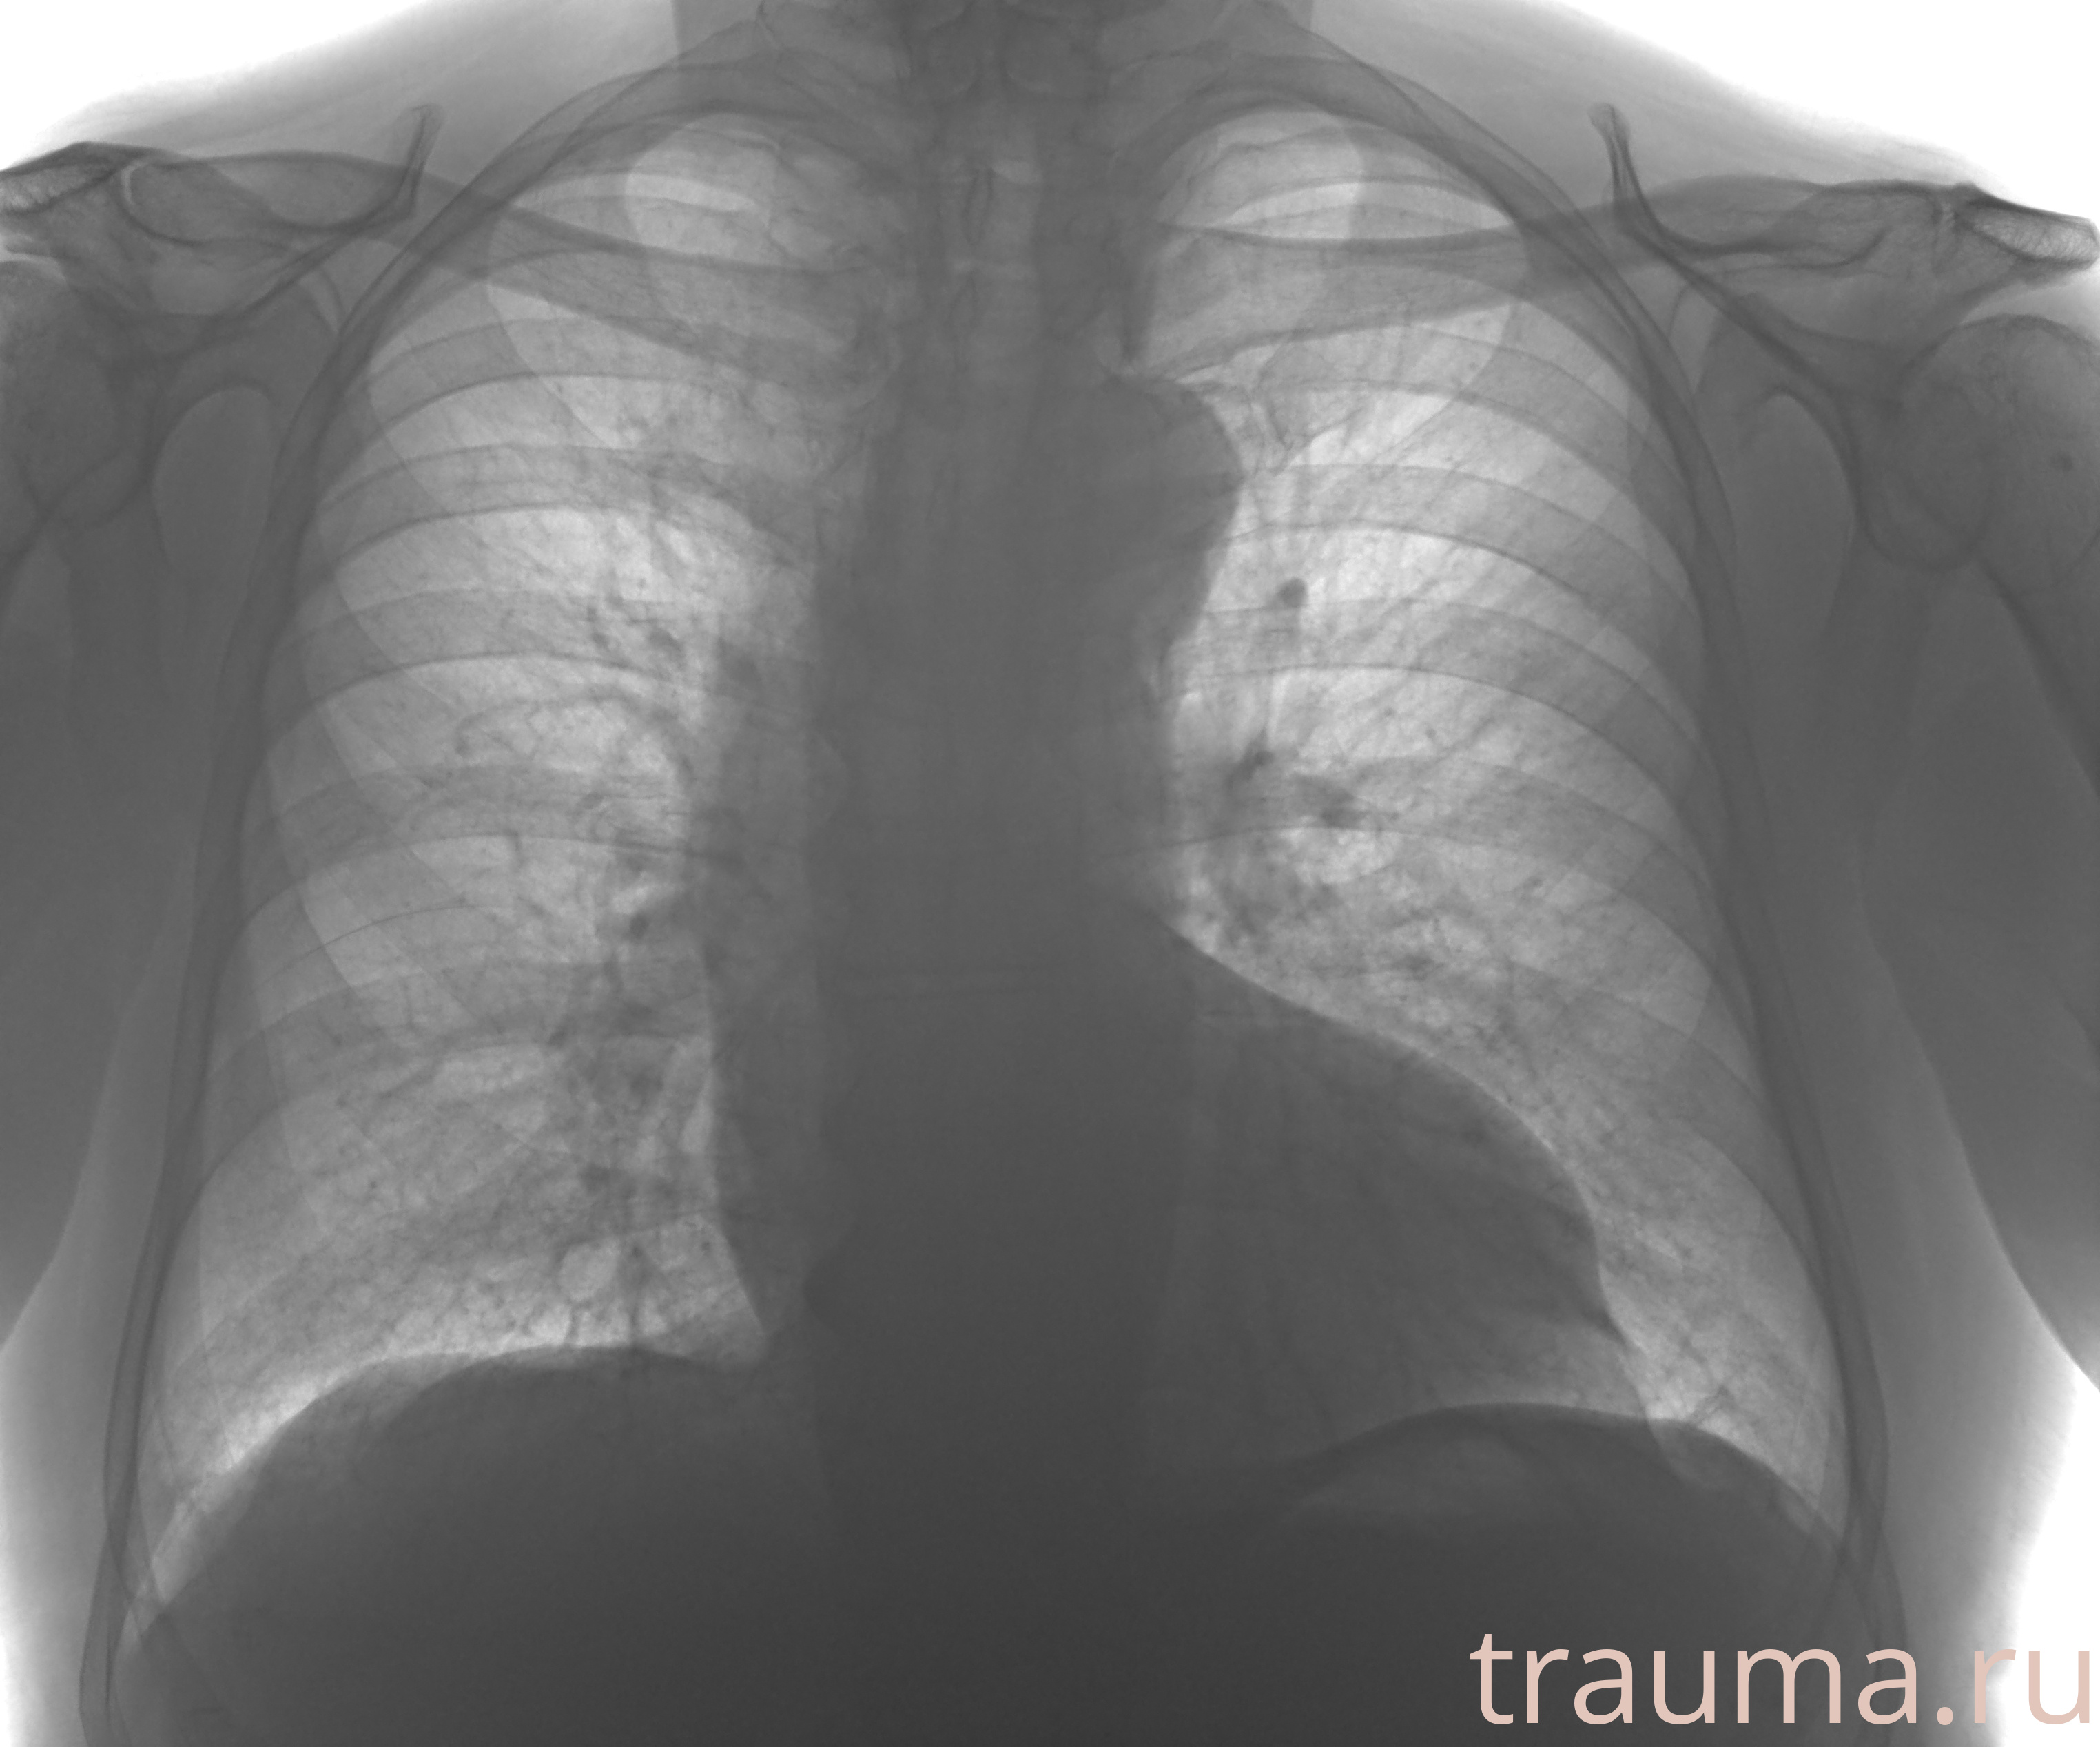

Рентгенограммы

Рентген на дому: по вашему адресу приезжает врач-рентгенолог, травматолог-ортопед с мобильным рентгеновским аппаратом, проводит диагностику травмы или заболевания, делает необходимые рентгенограммы, дает рекомендации по дальнейшему лечению. Получить качественные снимки в домашних условиях возможно благодаря уникальной методике, разработанной МосРентген Центром для института  Склифосовского

Яркость: 1   Контраст: 1   Инвертировать: 0 Увеличение: 1

Перетаскивайте мышь вверх/вниз для контраста, влево/право для яркости. Прокрутка колесом изменяет масштаб. Нажмите Сбросить для возврата к исходному изображению. При увеличении держите мышь в той области, которую хотите рассмотреть.